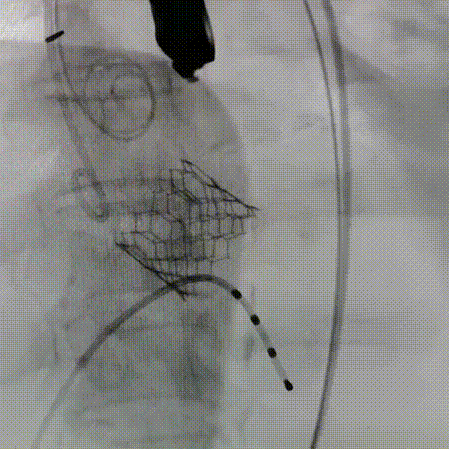

180bpm下置入23mm球囊扩张,沿导丝入26mm 爱德华经导管人工瓣膜输送系统,仔细定位,180bpm下释放瓣膜。释放后血压低,起搏心率,复查主动脉根部造影,轻度反流,LCX可疑血流不好,沿导丝入EBU3.25到位,造影冠脉血流通畅,复查术中食道心超,人工瓣膜位置满意,开放良好,压差3mmHg,轻度反流。手术圆满结束。

左冠造影